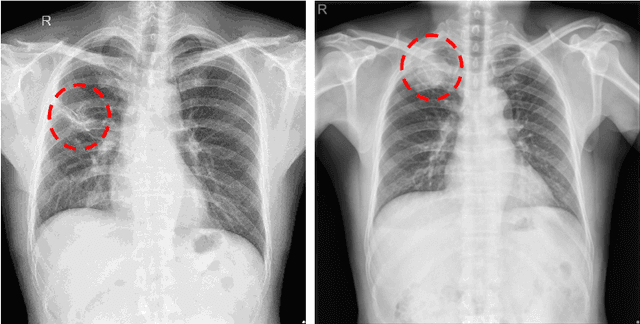

The current accessibility to large medical datasets for training convolutional neural networks is tremendously high. The associated dataset labels are always considered to be the real "ground truth". However, the labeling procedures often seem to be inaccurate and many wrong labels are integrated. This may have fatal consequences on the performance of both training and evaluation. In this paper, we show the impact of label noise in the training set on a specific medical problem based on chest X-ray images. With a simple one-class problem, the classification of tuberculosis, we measure the performance on a clean evaluation set when training with label-corrupt data. We develop a method to compete with incorrectly labeled data during training by randomly attacking labels on individual epochs. The network tends to be robust when flipping correct labels for a single epoch and initiates a good step to the optimal minimum on the error surface when flipping noisy labels. On a baseline with an AUC (Area under Curve) score of 0.924, the performance drops to 0.809 when 30% of our training data is misclassified. With our approach the baseline performance could almost be maintained, the performance raised to 0.918.